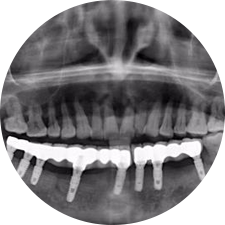

口腔種植是將人工牙根通過(guò)手術(shù)植入牙骨內(nèi),獲得牙槽骨牢固的支持,通過(guò)特殊的裝置和方式連接牙修復(fù)體,獲得與天然牙功能、結(jié)構(gòu)以及美觀相似的效果。

河北惟德口腔醫(yī)院擁有國(guó)內(nèi)豐富的半口/全口、即刻負(fù)重種植案例,十八年案例跟蹤分析,總結(jié)梳理出的各種不同類(lèi)型的種植案例,Nobel種植體系針對(duì)半口/全口缺牙患者,通過(guò)4-8顆種植體可快速達(dá)到牙齒重建,不僅植入種植體較少,節(jié)省費(fèi)用,手術(shù)時(shí)間更短。

術(shù)前患者CBCT口掃1:1三維重建,模擬手術(shù)過(guò)程及預(yù)測(cè)術(shù)后治療效果,確定每顆植體植入的適合的種植位點(diǎn)、深度及角度,有效避免損傷頜骨重要解剖結(jié)構(gòu),提高手術(shù)準(zhǔn)確度與安全性。

Noble口腔種植體系基本不受年齡限制,適用于缺牙修復(fù),也適用于牙槽骨萎縮、骨質(zhì)疏松、高血壓、糖尿病、超高齡的患者,即種即用,只需少量微小種植體,便可輕松微痛快速重建全口咬合,特殊力學(xué)設(shè)計(jì),針對(duì)許多年紀(jì)較大,骨質(zhì)條件差,身體耐受力差的缺牙老人也能完成“即種即用”,受到廣泛好評(píng)。

惟德口腔種植體系是以患者感受為中心,取代傳統(tǒng)種植牙手術(shù)需要翻瓣、打孔、縫合,術(shù)前、術(shù)中、術(shù)后的繁復(fù)流程,采用3D導(dǎo)航微創(chuàng)準(zhǔn)確種植技術(shù),通過(guò)數(shù)字化CAD/CAM掃描技術(shù)獲得缺牙患者口腔數(shù)據(jù),以數(shù)據(jù)為基礎(chǔ)重建口腔模型進(jìn)行模擬種植。

術(shù)前將患者口內(nèi)的CBCT數(shù)據(jù)及咬合關(guān)系上傳到計(jì)算機(jī)中,建立1:1三維重建,模擬手術(shù)過(guò)程及預(yù)測(cè)術(shù)后治療效果,找出較佳種植位點(diǎn)、深度及角度,獲取實(shí)際種植體在頜骨內(nèi)的具體三維位置,有效避免損傷頜骨重要解剖結(jié)構(gòu),大大降低手術(shù)風(fēng)險(xiǎn),提升種植成功率。